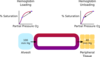

what are the differences between PLASMA, TISSUE FLUID & LYMPH in terms of hydrostatic pressure, oncotic pressure, cells, proteins and fats

HYDROSTATIC PRESSURE high hydrostatic pressure at arterial end in blood plasma, low in tissue fluid + lymph

ONCOTIC PRESSURE more negative in blood plasma, less negative in tissue fluid + lymph

CELLS RBCs & WBCs in blood plasma, WBCs in lymph

PROTEINS plasma proteins in blood plasma, low in lymph

FATS present in lymph